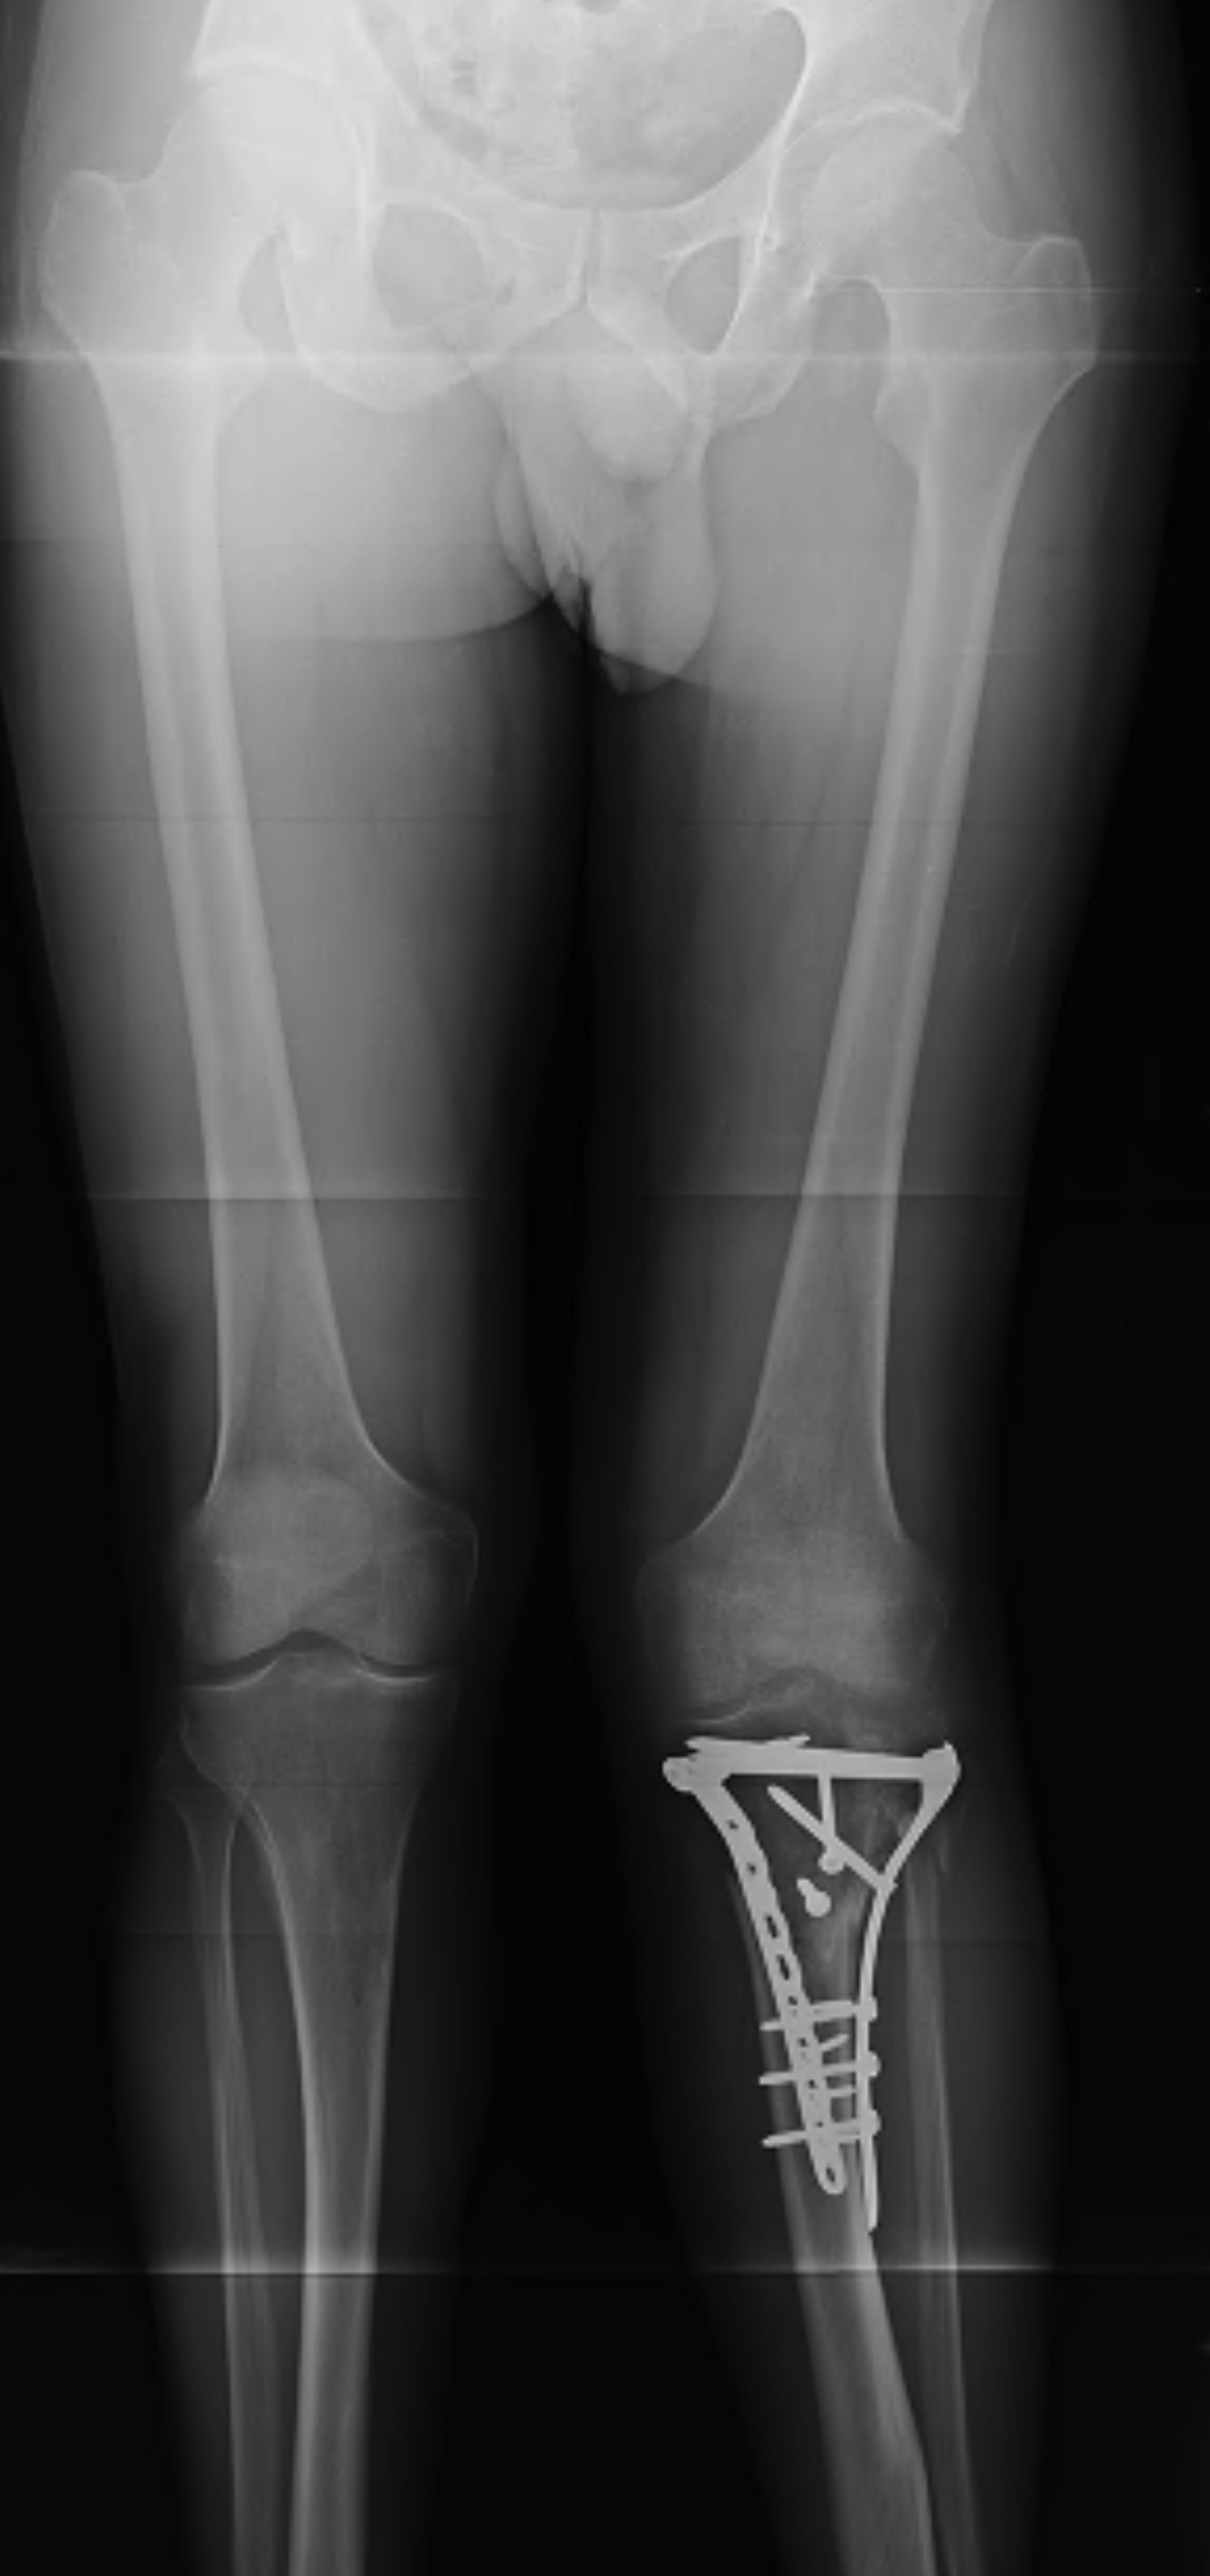

Type V Bicondylar

Options

1. Medial and Lateral plating

2. Circular Fixator

Canadian Orthopedic Trauma Society JBJS Am 2006

- RCT of ORIF (two plates) with circular external fixation in 83 knees

- comparable fracture reduction in both

- no difference in outcomes

- reduced blood loss / hospital stay / infection / reoperation with external fixation

- 7/40 (18%) of patients undergoing ORIF had an infection